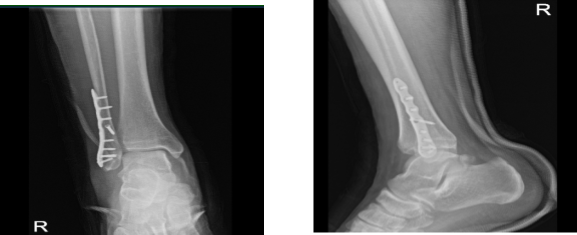

A week after the surgery, the patient visits the office with an X-Ray result, and there is a surgically treated fracture of the distal fibula. Fixation plates and multiple screws are in place. Fracture fragments are in good position and alignment.

Right tibia demonstrates intact cortical margins with no evidence of an acute fracture. Visualized aspects of the right talus, calcaneus and tarsal bones demonstrate intact cortical margins with no evidence of an acute fracture. There are no significant degenerative changes.

Ankle mortise is well maintained and no appreciable soft tissue swelling. There is no calcaneal plantar spur. Status post ORIF distal fibular fracture. Fracture fragments are in good position and alignment. The patient is doing well after the surgery, elevating, and icing.

X-ray right ankle - 2 weeks after surgery

X-ray right ankle – 2 weeks after surgery